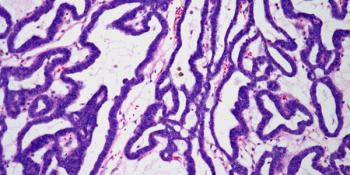

A 35-year-old woman was found to have a 4 cm nodule in the liver. After a biopsy is performed, what is your diagnosis?